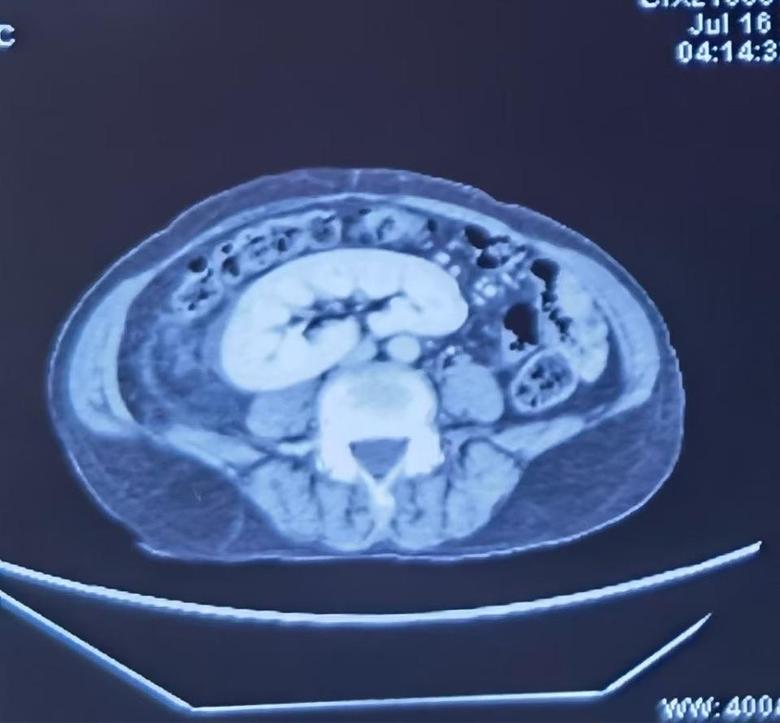

病例2

今日下午,2例巨大腹膜后肿瘤手术在我科顺利开展,腹膜后肿瘤发病率低,手术难度大,手术风险大,国内开展相关手术单位为数不多,我院腹膜后肿瘤手术量连续数年位居国内前列,在腹膜后肿瘤领域团队具有丰富经验,巨大腹膜后肿瘤手术开展,表明该类手术在我院已经成为常态。并且将继续保持国内在领先水平。